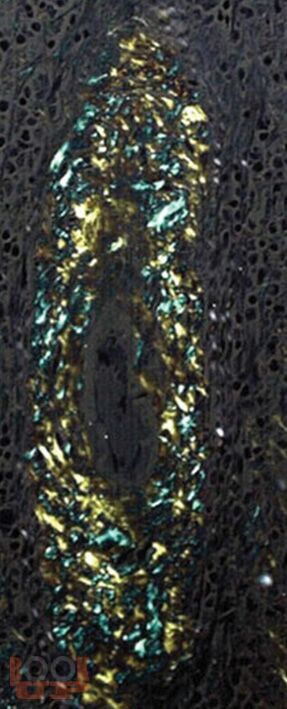

Учебное пособие посвящено клинико-морфологическим аспектам классификации и диагностики амилоидоза с использованием современных методов морфологии и иллюстративного материала. В пособии представлены краткий теоретический материал, ситуационные задачи с примерами решения и для самостоятельного выполнения, тестовые задания и ответы на них, что позволит студентам проводить диагностику амилоидоза с целью установления диагноза, способствует оценке морфофункциональных, физиологических состояний и патологических процессов в организме человека для решения профессиональных задач.